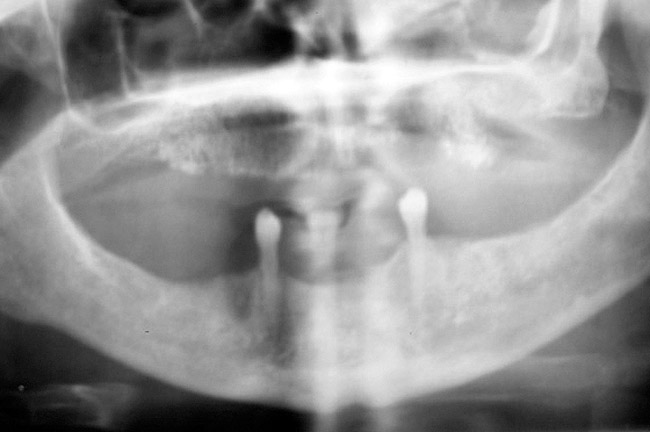

After all dental infections have been removed, patients can initiate IV therapy. Dentists should follow up regularly with these patients during their bisphosphonate therapy, preferably once a month. After patients are off bisphosphonate therapy for 2 months, their radiograph series should be updated. The radiographs should be viewed for signs of sclerosis of the lamina dura or widening of the periodontal ligament because these are usually the first places where signs of bisphosphonate toxicity and osteonecrosis can be seen.19

Figure 11  The radiograph shows 80% bone loss.

Figure 11

Figure 18  Panoramic radiograph showing decreased bone density.

Figure 18